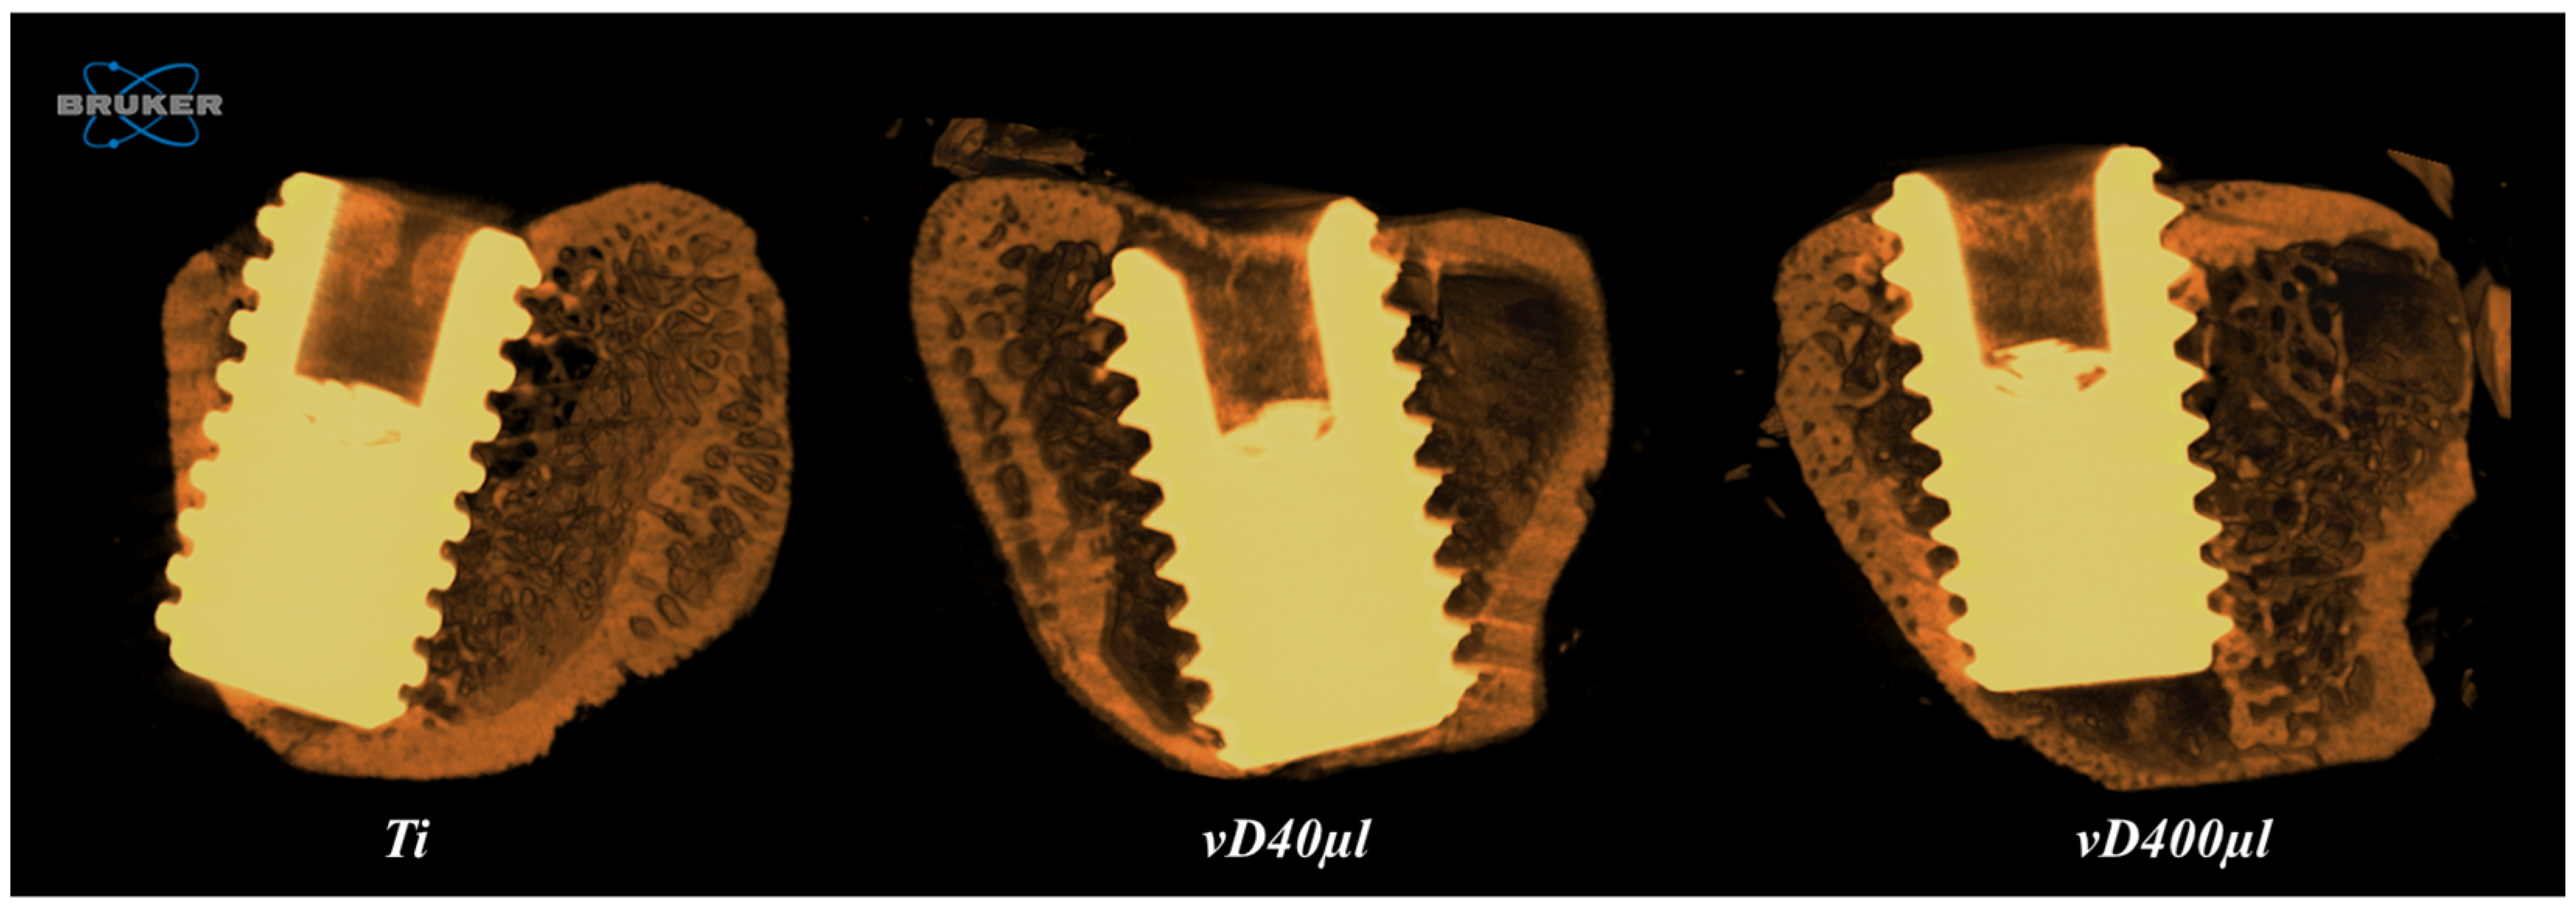

3.2. Microtomography Analysis (Micro-CT)

| Ti | vD40µl | vD400µl | |

|---|---|---|---|

| BV/TV (%) | 40.1 ± 13.28 | 46.8 ± 8.97 | 54.7 ± 2.87 |

| Po.Tot (%) † | 61.43 ± 12.01 | 59.26 ± 3.61 | 45.32 ± 2.87 |

| IS (mm2) † | 6.71 ± 1.95 | 8.62 ± 0.61 | 12.54 ± 1.56 |

| Tb.Th (mm) | 0.094 ± 0.008 | 0.092 ± 0.004 | 0.094 ± 0.003 |

| Tb.N (1/mm2) † | 3.82 ± 0.73 | 4.38 ± 0.23 | 5.75 ± 0.52 |

| Tb.Sp (mm) † | 0.108 ± 0.005 | 0.107 ± 0.004 | 0.092 ± 0.005 |

| Ti | vD40µl | vD400µl |

|---|---|---|

| 6.98 ± 1.181 A | 8.91 ± 2.091 AB | 9.65 ± 1.526 B |